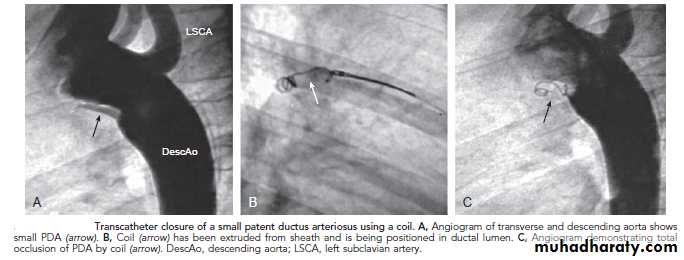

PDA requires surgical or catheter closure. Most PDAs can be closed in the catheterization laboratory by either coil embolization or a PDA closure device.

Transcatheter closure of a small PDA